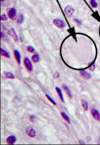

Identify

Chromophils

- large cells, much RER,well developed Golgi complex, many secretion granules (contain hormone)

Idenitfy circled structure

Chromophobe

- chromophils that have released their specific hormones and are “degranulated”

- therefore, stain poorly